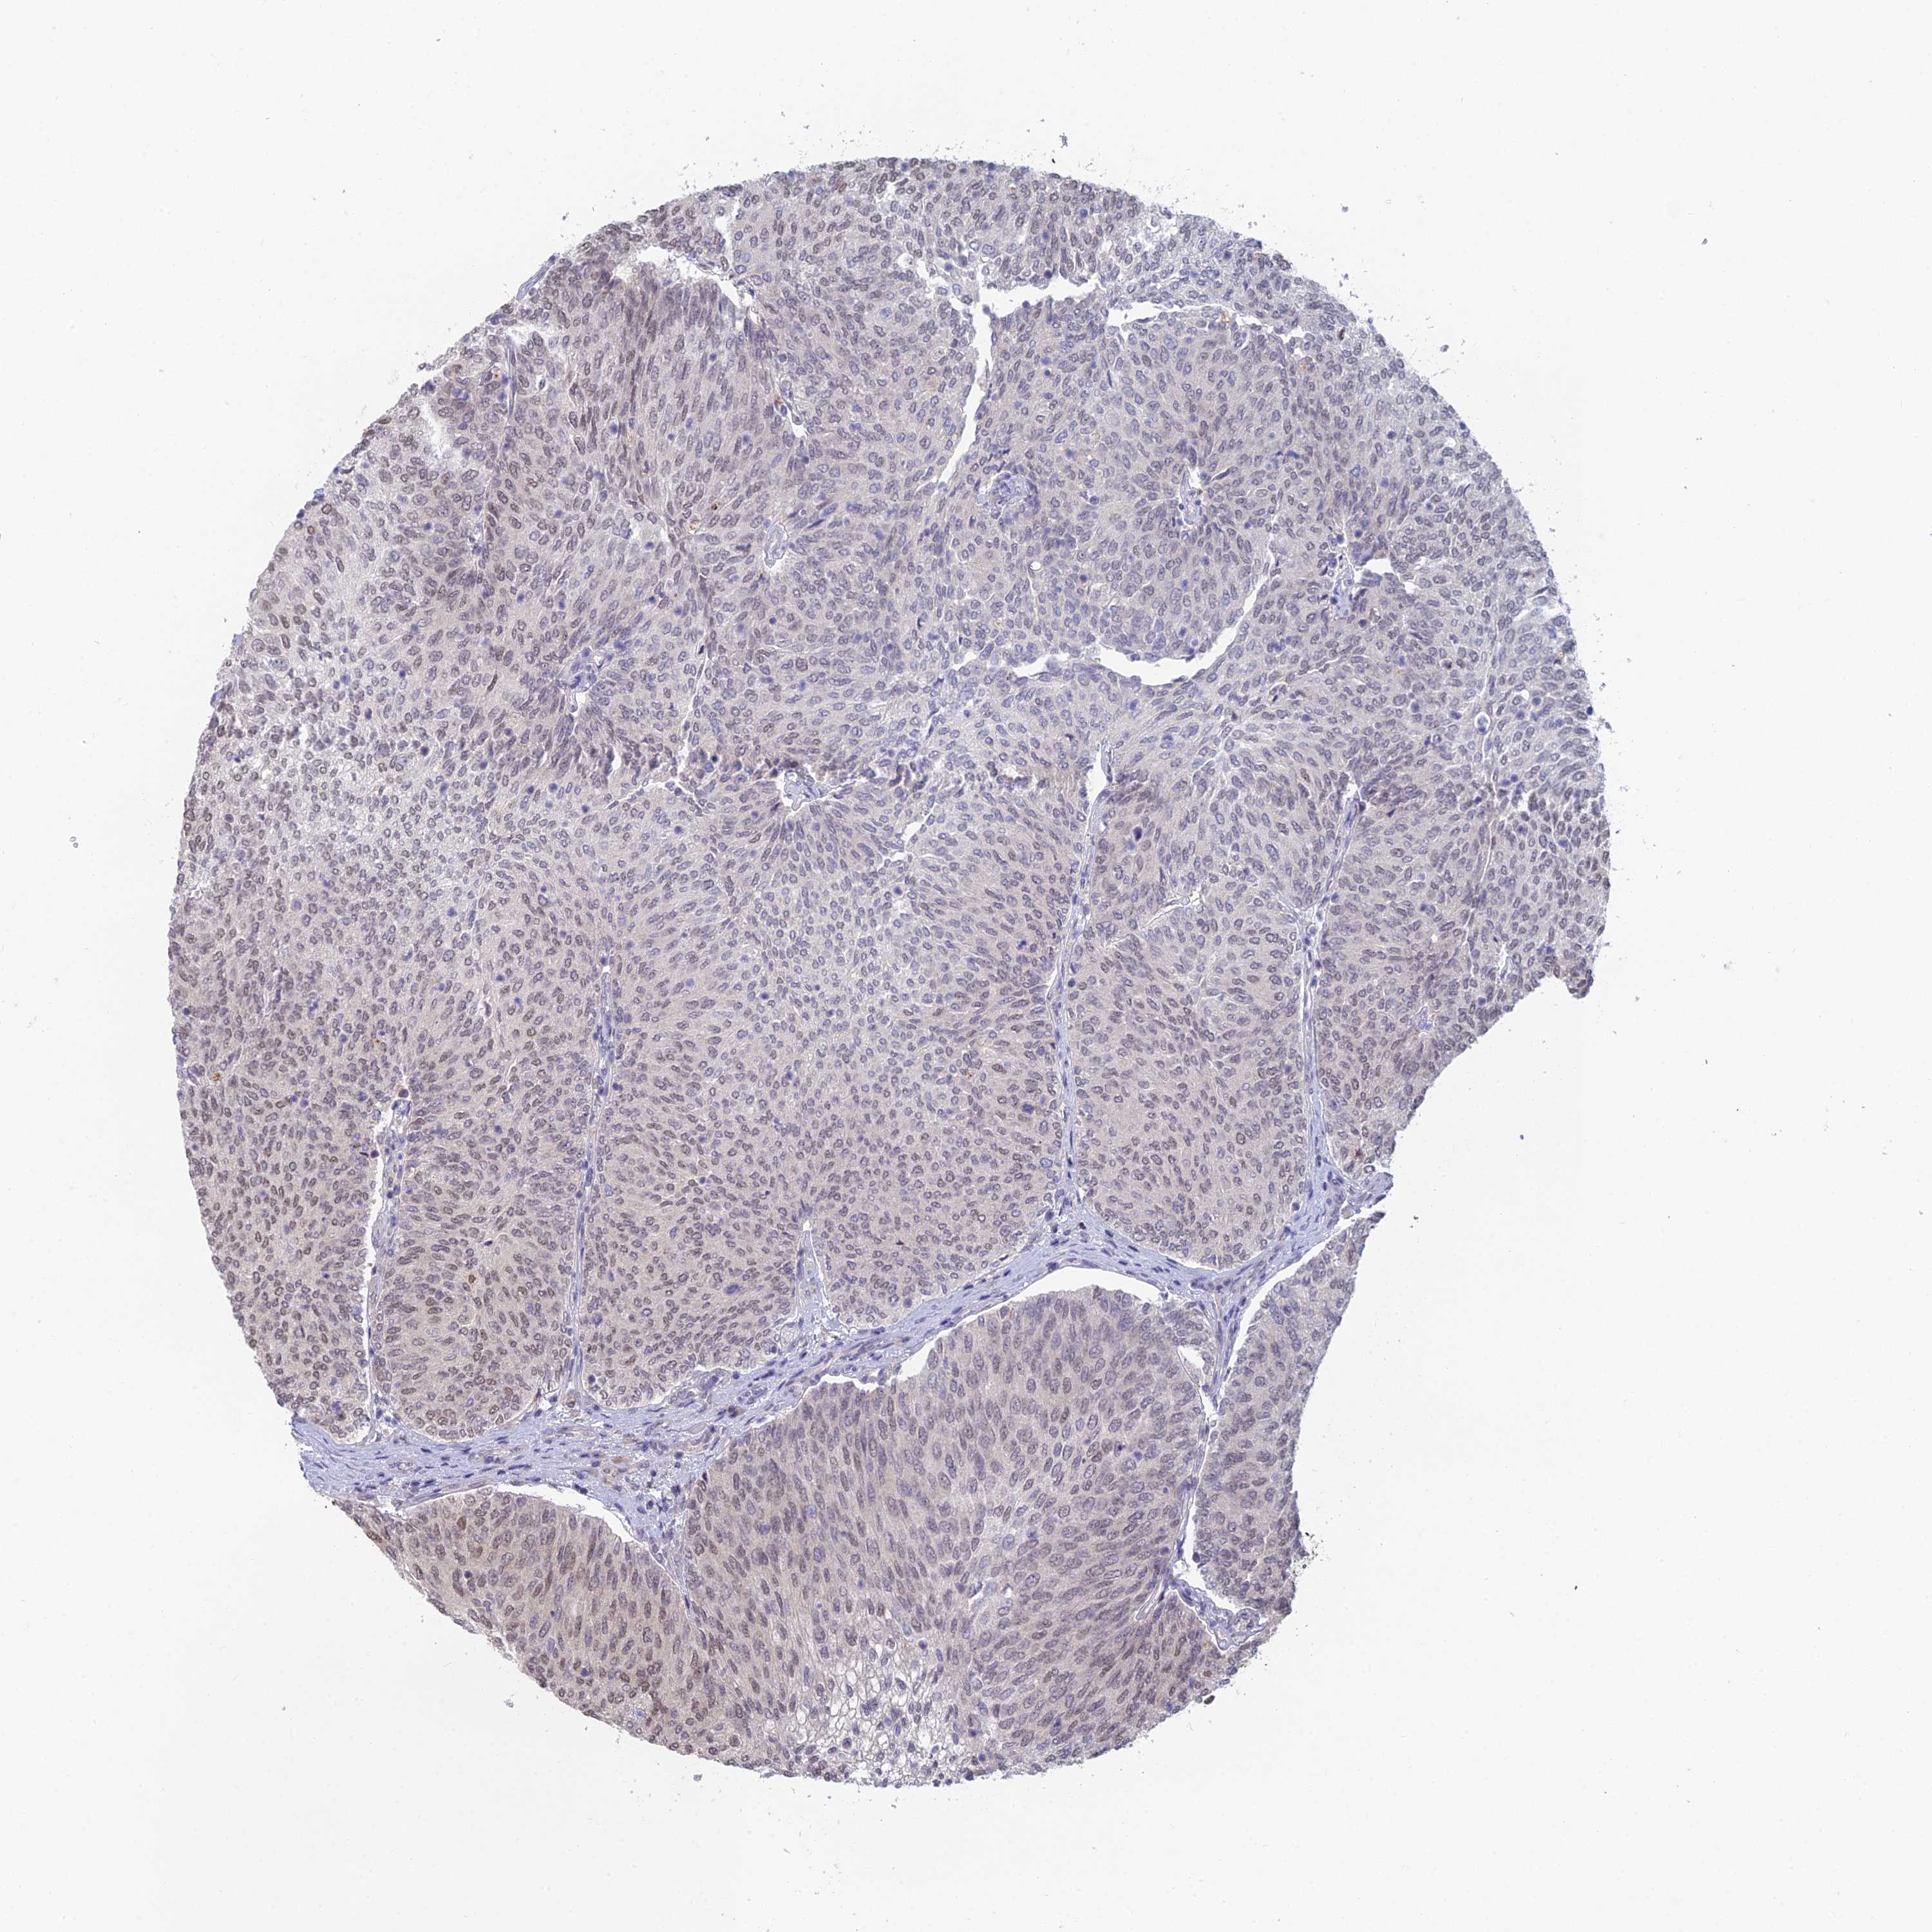

UROTHELIAL CANCER - Protein expressioni

A mouse-over function shows sample information and annotation data. Click on an image to view it in a full screen mode. Samples can be filtered based on level of antibody staining by selecting one or several of the following categories: high, medium, low and not detected. The assay and annotation is described here.

Note that samples used for immunohistochemistry by the Human Protein Atlas do not correspond to samples in the TCGA dataset.

Antibody stainingi

Antibody staining in the annotated cell types in the current human tissue is reported as not detected, low, medium, or high, based on conventional immunohistochemistry profiling in selected tissues. This score is based on the combination of the staining intensity and fraction of stained cells.

Each image is clickable and will lead to virtual microscopy that enables deeper exploration of all samples and also displays staining intensity scores, fraction scores and subcellular localization as well as patient and tissue information for each sample.

Antibody HPA043375

Antibody HPA043389

Urothelial carcinoma, High grade

Urothelial carcinoma, Low grade